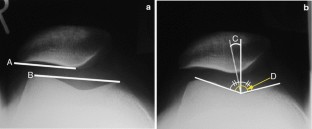

Before MPFL reconstruction, the patella in all patients was shifted laterally throughout the entire range of knee motion. Immediately after MPFL reconstruction, patellar malalignment was corrected in all cases. On second-look arthroscopy, two different patellar tracking patterns were observed. In 9 knees, the patella was located on the center of the femoral groove throughout the range of motion. Meanwhile, in the remaining 16 knees, the patella was shifted laterally at knee extension and migrated to the center of femoral groove with increased knee flexion. No significant deteriorations in chondral status were seen on second-look arthroscopy.